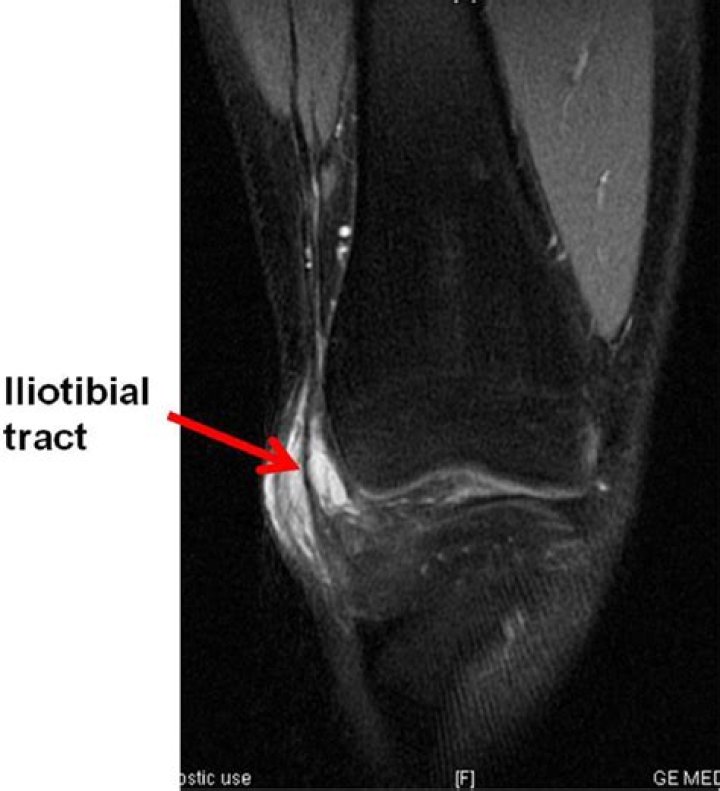

In severe cases, magnetic resonance imaging (MRI) may be helpful in identifying the extent of inflammation of the ITB. Findings on MRI most commonly inclu...